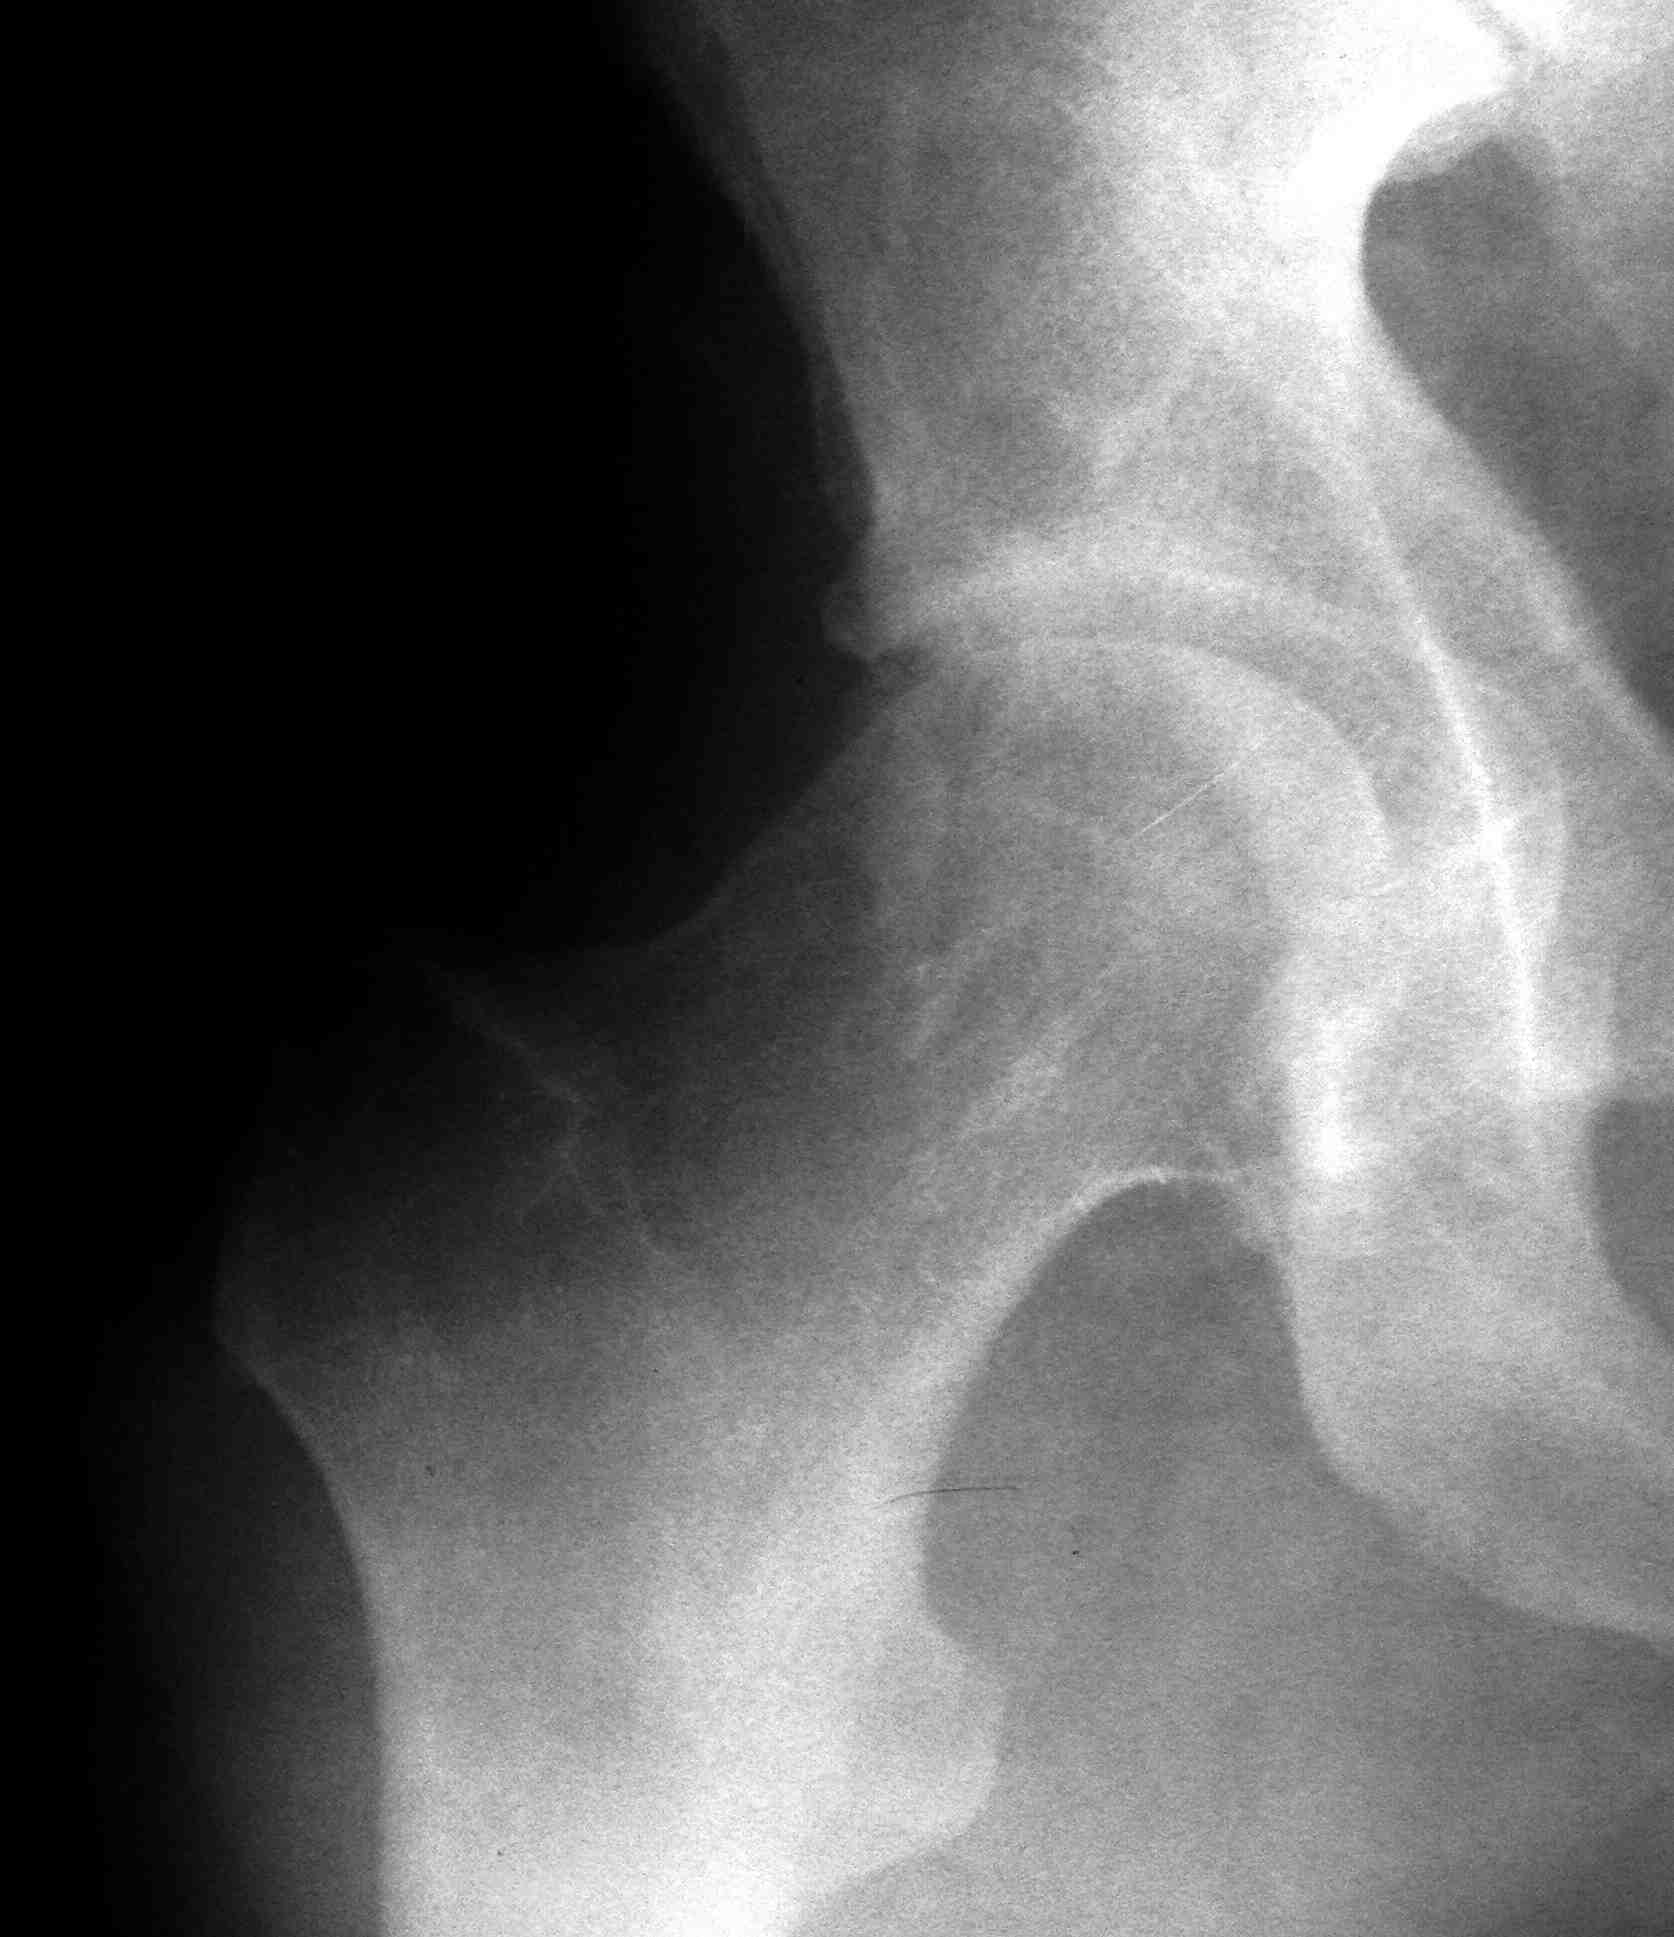

первым этапом сделали синтез задней стенки, дистракционный аппарат на ногу, снимки низкого качества, завтра постараюсь приложить нормальный рентген и КТ

Добрый день, коллеги! Повреждение вертлужной впадины вероятнее всего 62-А1.2 чистый переломовывих, оскольчатый перелом задней стенки, при этом внутрисуставной фрагмент, является частью артикулирующей поверхности ацетабулюм, а следовательно его необходимо извлечь и поместить на место, иначе мозаика может не собраться. Про FAI временно можно не вспоминать (не до него), поскольку наиболее тяжелое повреждение голени требует адекватного вмешательства.На представленных рентгенограммах таза после операции все отлично, полную картину даст КТ.